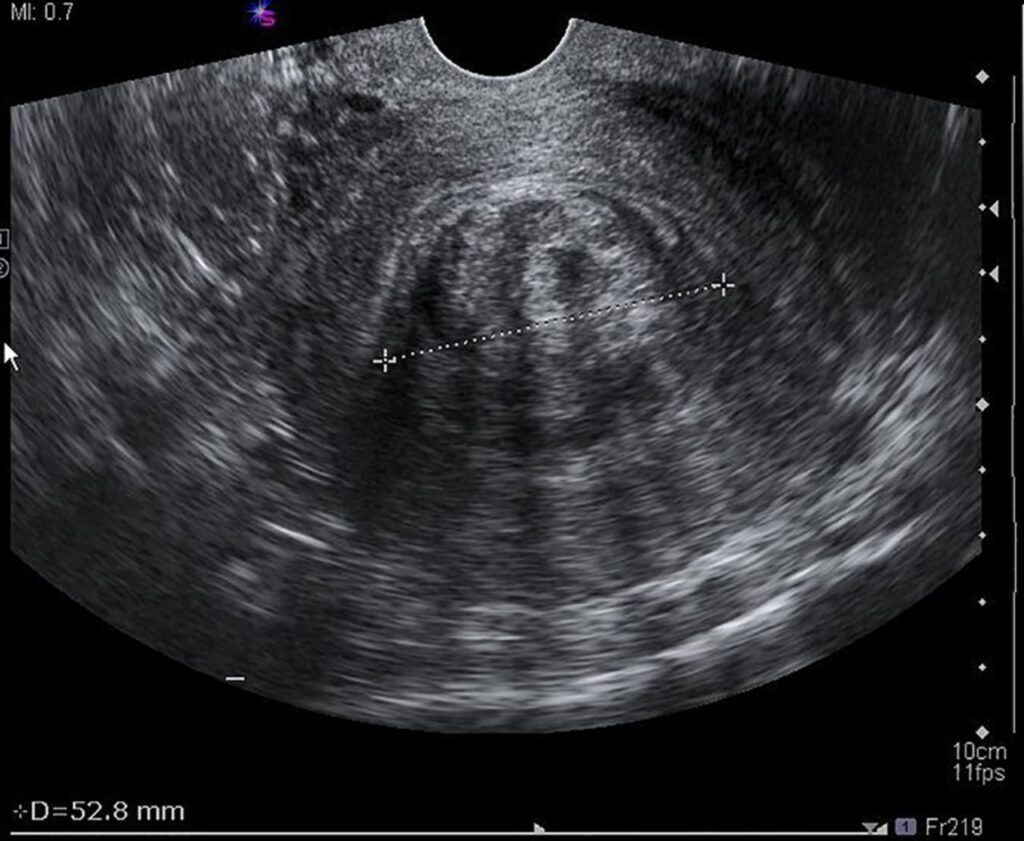

The woman, who has been battling fibroids for several years, says the condition has steadily worsened, affecting her health, daily life, and fertility. Fibroids are non-cancerous tumours that grow in and around the uterus and are known to disproportionately affect Black women. In her case, the growths have caused chronic pain, heavy bleeding, and increasing concern about long-term reproductive damage.

After seeking medical advice locally in St Vincent and the Grenadines, she was advised that specialised surgical care was not readily available and that treatment abroad was necessary. Like many Vincentian women facing similar diagnoses, she has been forced to look to Barbados for treatment.

She is scheduled to undergo surgery at Bayview Hospital, a procedure doctors say is critical to preserving her health and any remaining chance of future fertility. The total cost of the surgery and associated expenses runs into tens of thousands of dollars.